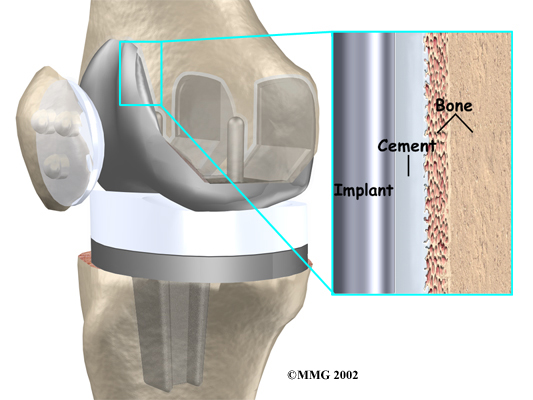

A is held in place by a type of epoxy cement that attaches the metal to the bone. An has a fine mesh of holes on the surface that allows bone to grow into the mesh and attach the prosthesis to the bone.

Both are still widely used. In many cases a combination of the two types is used. The patellar (kneecap) portion of the prosthesis is commonly cemented into place. The decision to use a cemented or uncemented artificial knee is usually made by the surgeon based on your age, your lifestyle, and the surgeon's experience.

The tibial component (bottom portion) replaces the top surface of the lower bone, the tibia. The stem of the tibial component used in revision surgery is usually much longer than the type used for primary knee replacements. This is because the bone of the tibia is usually not the same as when the initial replacement was done. The bone may be weaker, or there may be areas inside the tibia where bone is missing. A longer stem can reach further down the tibial canal and distribute your body weight better. It also gives the body a greater surface area for healing, which can improve fixation of the implant to the bone inside the tibia.

The femoral component (top portion) replaces the bottom surface of the upper bone (the femur) and the groove where the patella fits. Like the tibial component used in revision, the femoral component often has a long stem.

The patellar component (kneecap portion) replaces the surface of the patella where it glides in the groove on the femur.

The tibial component is usually made of two parts: a metal tray that is attached directly to the bone, and a plastic spacer that provides the slick surface. The femoral component is made of metal. In some types of knee implants, the patellar component is made of a combination of metal and plastic.